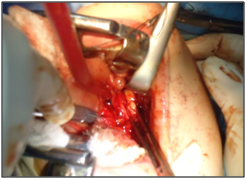

Figure 7  Blunt dissection is used to release the submandibular gland surrounding structures.

The previous separation of the posterior margin of mylohyoid allows to visualize the surface portion of the submandibular gland. Blunt dissection is used to release the submandibular gland of surrounding structures. Applying transcervical submandibular gland pressure on the floor of the mouth helps viewing, and gland is removed carefully and hemostasis is performed. A drain can be inserted through the incision, whereafter the mucosa is reapproximated with an absorbable suture, thus concluding the surgical procedure.